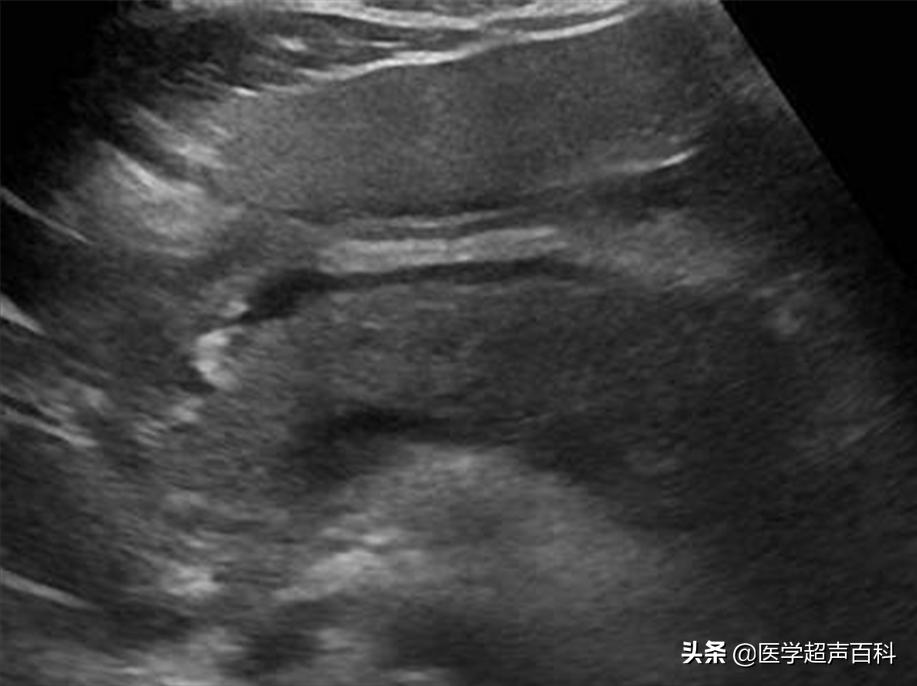

急性胰腺炎声像图表现

(1)胰腺弥漫性或局限性增大,可失去正常形态,轮廓不清。

(2)内回声减低,呈弥漫分布的弱点状,中间有强弱不均、形态不整、边界不清的片状回声。严重水肿时呈透声暗区,似囊肿声像图。

(3)多伴胰腺区胃肠气体增多,以胰头区更甚,使探查更为困难。